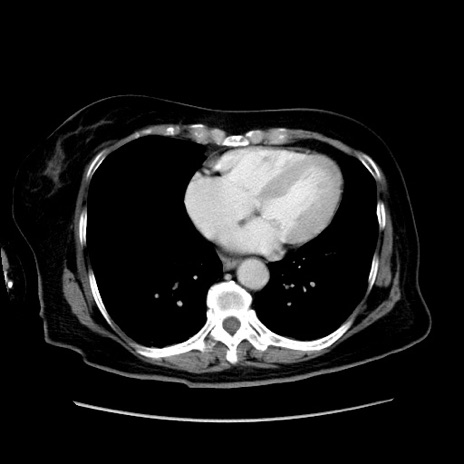

冠状断像

【症例】80歳代女性

【主訴】下腹部痛

【現病歴】約8時間前より下腹部痛の出現あり、救急外来受診。

【既往歴】両側付属器切除

【身体所見】意識清明、下腹部正中に手術痕あり、その部位に一致して圧痛と反跳痛あり。腸蠕動音は亢進。

【データ】WBC 9300、CRP 0.15